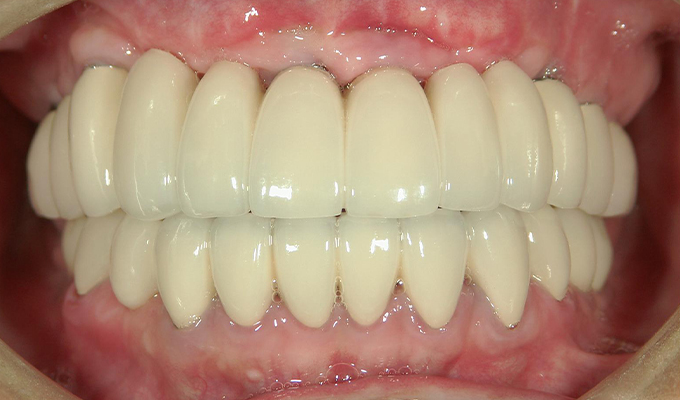

case3インプラントとハイブリットセラミックスの症例

初診時(2012年)

初回メンテナンス時(2014年)

最新メンテナンス時(2024年)

- 初診時の年齢

- 50代男性(2012年)

- 主訴

- 左上の前歯が欠けた。右の奥歯は3年前に抜けてそのままになってる。全体的に治療したい。

- 治療内容

- 全体的に歯周病があり(平均ポケット数値6~7mm)、そのせいで動揺している歯も多数あったためまず歯周病の治療を行いました。

平均ポケット数値が2~3㎜になったところで補綴治療を開始しました。歯のない部分はインプラントを入れ、ブリッジはハイブリットセラミックスで入れました。

2014年に治療が終わった後もメンテナンスに定期的に通っていただきナイトガードも使用していただいてます。きれいな状態が維持されています。